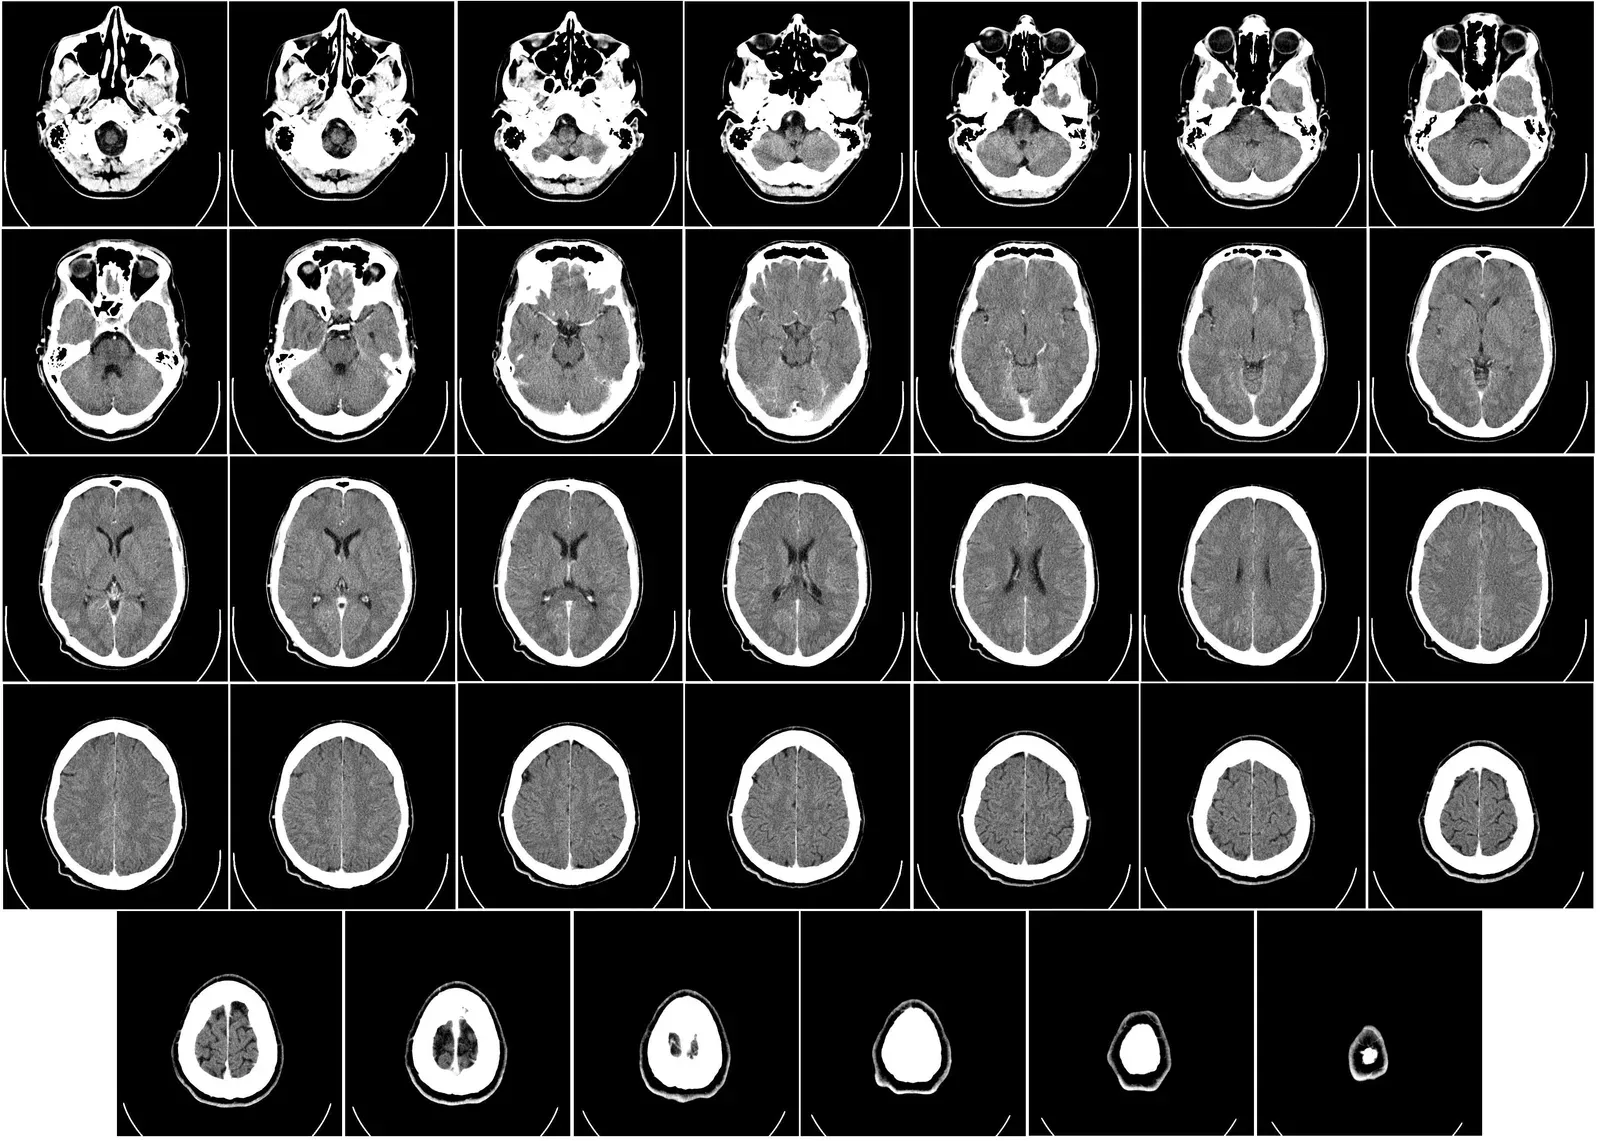

It still surprises many people to hear that the adult brain is not a finished product, but a living construction site. The first hints came from studies of animals, where researchers found fresh, immature neurons in the hippocampus, a region crucial for learning and memory. That discovery alone overturned long-standing dogma, but the real shock came when similar patterns were reported in human brains, including those of older adults. Instead of a barren landscape, the hippocampus looked more like a garden where new seedlings occasionally appear among the older trees. The number of new neurons may not be massive, but their very existence in later life changes the story of what aging means.

More recently, careful post-mortem studies of human brain tissue from people in their seventies and eighties have found cells that appear to be young neurons, still going through their maturation process. Researchers use molecular markers – specific proteins and shapes – to distinguish these newcomers from the long-established cells around them. In several studies, brains from older adults who were cognitively healthy still showed signs of ongoing neurogenesis in the hippocampus. Even in people who had early-stage Alzheimer’s disease, the machinery for making new neurons was not entirely shut down, though it appeared less active. These hidden clues collectively suggest that neurogenesis in later life is not a myth; it is just quieter, more vulnerable, and easily overshadowed by disease or lifestyle factors.

Human research was slower and more complicated, because scientists cannot label cells in living brains the way they can in lab animals. Instead, they developed creative strategies, such as analyzing brain tissue from people who had been exposed to atmospheric nuclear testing decades ago, which left a distinct carbon signature in newly formed cells. These kinds of studies suggested that some brain regions, especially the hippocampus, continue to incorporate new neurons throughout adulthood. The rate of this process appears to decline with age, and different labs still debate exactly how robust it is in very old age, but few serious researchers now claim it does not happen at all. In science, that kind of shift – from flat denial to nuanced argument over magnitude – is usually a sign that a field has genuinely moved forward.